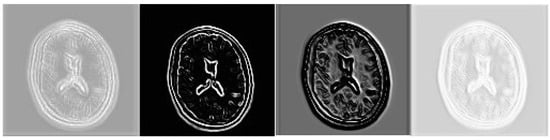

- The image gradient is employed as a regularization item in the loss function. In a correctly restored image, the edges and texture (related to the image gradients) should be accurate. The regularization term, which is induced by additional sources of information, helps recover high-frequency details. , where is defined asin which denotes the gradient detector, and is the gradient magnitude of image x.

- The alternative approach to incorporating image gradient in the SR process is to concatenate the gradient maps with the input LR image y as a joint input of the network. Thus, the mapping function is

3.1. Gradient Modeling (GM) Subnet